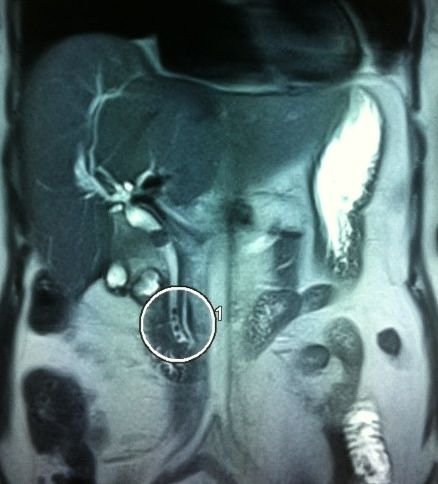

- Zədələnmələrin olub-olmamasını, yеrini və xaraktеrini dəqiqləşdirmək üçün xolangioqrafiya еdilir. MRT ilk seçimdir, lakin dəqiqləşdirmə üçün adətən kontrastlı xolangioqrafiya edilir: əməliyyat vaxtı əməliyyatdaxili xolangioqrafiya, əməliyyatdan sonra isə endoskopik və ya perkutan xolangioqrafiya.

- Öd yollarına yeridilən kontrastın kənara çıxması və ya “blok” (bağlanma) zədələnməni təsdiqləyən əlamətləridir.

- Xolangioqrafiyada biliar ekstravazasiya və ya blok

Əməliyyatdan sonra tapılan bağlamalarda xəstə ixtisaslaşmış klinikaya göndərilir. Belə xəstələrdə ilk olaraq MRT edilərək bağlanma yeri dəqiqləşdirilir. MRT yetərsiz olarsa ERXPQ edilə bilər. Əlavə olaraq KT angioqrafiya və ya dopler USM ilə arteriya zədələnməsini yoxlamaq lazımdır. Diaqnostik işləmlərdən sonra zədələnmə yerinə və ağırlaşmalara görə müalicə taktikası seçilir. Magistral axacaqların bağlanmasında xəstə nəzarət altında saxlanılır, anastomoz üçün 2-3 həftə gözlənilir və ağırlaşmaların profilaktikası həyata keçirilir. Bu müddət öd yollarının genişlənməsi, divarının qalınlaşması, iltihabın sönməsi və anastomoz üçün əlverişli şərait yaratmaq məqsədi daşıyır. Gözləmə müddətində ağırlaşmaların profilaktikası və müalicəsi üçün aşağıdakı tədbirlər həyata keçirilir: